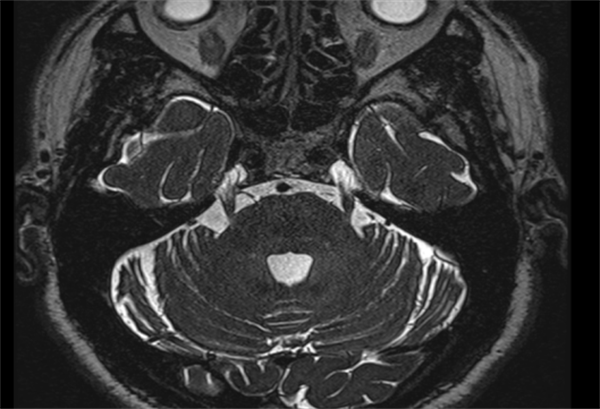

疼痛每个人都体会过,但号称“天下第一痛”的三叉神经痛却没几个人能懂。75岁刘大爷(化名)不幸得了右侧三叉神经痛,不敢说话,不敢吃饭,甚至痛不欲生。近日,老虎机app (简称老虎机app )杨超教授团队通过运用纯内镜下三叉神经微血管减压术,帮助患者解决疼痛烦恼。术后的刘大爷状态恢复良好,现在面部不疼,也能正常吃饭了。据了解,刘大爷长期饱受右侧面部疼痛的折磨。2021年,...